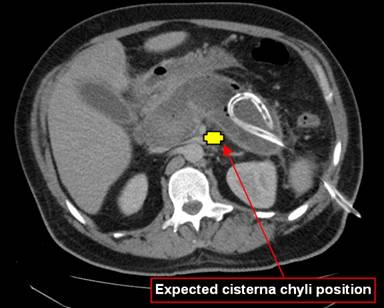

A 37-year-old Caucasian male was transferred to our service for management of severe acute biliary pancreatitis. His clinical course necessitated intensive care admission and was treated with percutaneous image guided pancreatic bed drainage and antibiotics (Figure 1). He developed a resistant Enterococcus infection (vancomycin resistant Entercocci) and was treated with meropenem, linezolid and fluconazole. Aetiological work up included a magnetic resonance cholangiopancreatography (MRCP) showing a thickened gallbladder with multiple calculi and a dilated common bile duct. Subsequent endoscopic retrograde cholangiopancreatography (ERCP) revealed sludge in the common bile duct which was cleared. Given his severe course associated with significant collection, his cholecystectomy would be performed on an interval basis. Therefore, an endoscopic sphincterotomy was performed. A pancreas duct stent was not employed in this case.

Figure 1. CT abdomen showing haemorrhagic pancreatitis with drain in situ. |

Gaspare Asello, who first documented the lymphatic system, described a cream coloured liquid as he transected the “nerve like” lacteals in a dog [8]. Lymph travel in lymphatics, which returns interstitial fluid back to the circulation. Lymphatics from the intestinal tract merge with those draining the lower limbs to form the saccular cisterna chyli at the level of L1 and L2 which joins with the thoracic duct in the thorax [7]. These vessels are vulnerable to damage along its course especially at the cisterna resulting in chylous ascites. Surgery related chylous ascites are rare and occur during extensive retroperitoneal dissection where the cisterna is vulnerable. However, damage to major lymphatics during cholecystectomy that will result in chylous ascites is rare. It is difficult to explain how major lymphatic leak can occur during cholecystectomy. Usually minor lymphatic channels are encountered. We postulate that the degree of injury to lymphatics during cholecystectomy is small and that a derangement of anatomy must exist, making it more vulnerable to the development of chylous ascites.

The cisterna chyli lies at the level of the pancreatic head and inflammation can cause chylous compression and direct enzymatic damage to the cisterna [5]. Our patient’s recent severe pancreatitis may be a factor in his post operative chylous ascites. We hypothesize, supporting the only other case post pancreatitis, that acute pancreatitis causes compression of the cisterna chyli resulting in backflow and dilatation of lymph vessels upstream [2]. This pre-existing diversion of flow pre-existed in the hepatoduodenal ligament and the use of force device (LigaSureTM, Covidien, Boston, USA) contribute to the development of chylous ascites in cholecystectomy. There should be no risk to the cisterna itself. This derangement in anatomy can predispose lymph vessels to operative damage or spontaneous chyle leak. Incidence of post-pancreatitis chylous ascites is unknown as most are asymptomatic and therefore undetected. In this case chylous ascites was detected day two post-cholecystectomy and is suggestive of operative damage to predisposed vessels.